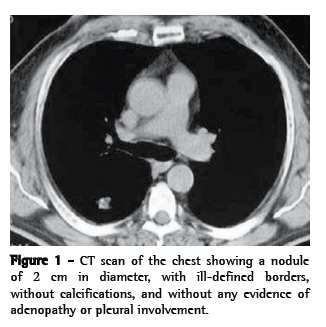

The patient had been asymptomatic until March of 2008, when he underwent a routine chest X-ray. The chest X-ray revealed hypodensity consistent with a pulmonary nodule located in the right lower lobe. This finding was subsequently confirmed by a CT scan taken in April of the same year (Figure 1). The nodule was 2 cm in diameter, had no calcifications, and had ill-defined borders. There was no evidence of adenopathy or pleural involvement.